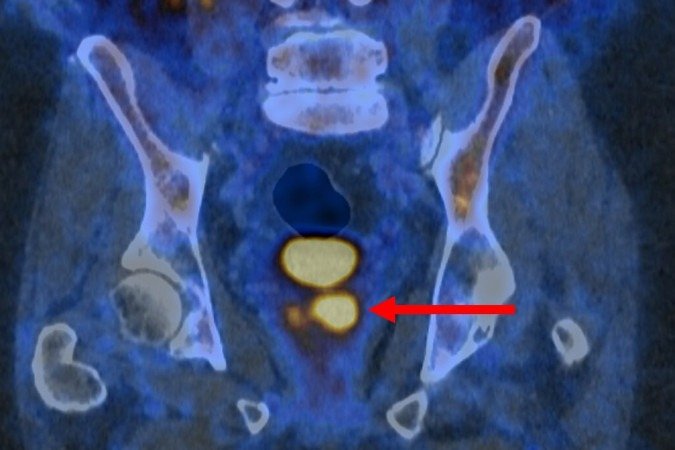

O exame PET/CT (tomografia por emissão de Pósitrons/tomografia computadorizada) com PSMA identifica células agressivas presentes na próstata, que são potencialmente prejudiciais e podem precisar de tratamento. Isso é possível graças a uma molécula que se liga a essas estruturas e as faz brilhar, aparecendo como pontos luminosos na imagem. O estudo afirma que isso também pode ajudar a reduzir o risco de sobrediagnóstico.

O ensaio descobriu que a tomografia por emissão de pósitrons (PET/CT) com PSMA podia identificar pessoas que não tinham câncer ou cujo tumor era de tão baixo risco e com crescimento tão lento que provavelmente nunca causaria danos. Esses pacientes não precisaram de biópsia. A nova abordagem reduziu pela metade o número de pessoas submetidas ao exame invasivo, sem deixar de detectar nenhum câncer maligno.

A abordagem também beneficiou os pacientes que ainda precisavam de biópsia. Os resultados da tomografia garantiram que o procedimento fosse direcionado às áreas suspeitas identificadas no exame de imagem, a fim de minimizar complicações e aumentar a precisão.